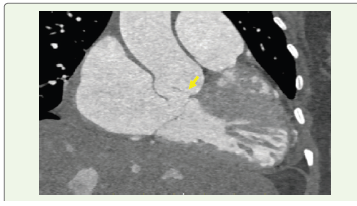

Figure 1:Coronal multiplanar reformatted CT image demonstrating the

fistulous tract extending from the non-coronary sinus into the right atrium

(arrow).

CT angiography demonstrated a focal aneurysmal dilatation

arising from the non-coronary sinus of Valsalva, measuring

approximately 18 × 14 mm. A well-defined rupture defect measuring

approximately 12.5 × 11.4 mm was identified in the wall of the

aneurysmal sac. Through this defect, contrast was seen directly

opacifying the right atrium, confirming the presence of a fistulous

communication.The aneurysmal sac was noted to protrude into the right atrium, producing indentation of the adjacent tricuspid valve leaflet. There was significant dilatation of the right atrium and inferior vena cava, with associated hepatic venous congestion. The main pulmonary artery was dilated, measuring approximately 3.9 cm, suggestive of pulmonary hypertension. Mild pericardial effusion and cardiomegaly were also present.